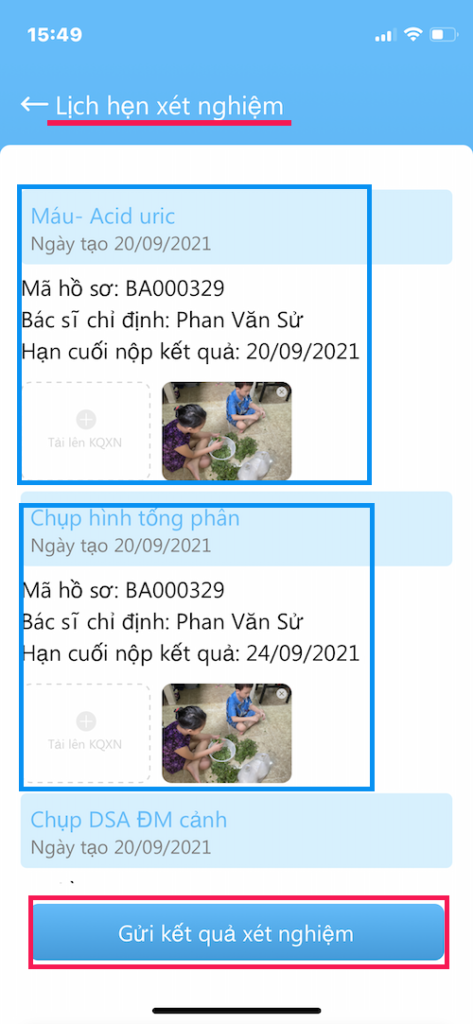

(3) Lịch hẹn xét nghiệm: Nơi xem và tải lên các xét nghiệm

LỊCH HẸN XÉT NGHIỆM

Các xét nghiệm Bác sĩ yêu câù cần làm

- Nơi gởi kết quả cho Bác sĩ

- Các xét nghiệm trước đây cũng có thể xem tại đây

- Gởi kết quả xét nghiệm bằng hình ảnh ( chụp trực tiếp hoặc lấy từ thư viện ảnh)

- Hãy kiểm tra xét nghiệm mà Bác sĩ yêu cầu phải làm

- Trường hợp bệnh nhân chưa nhận được toa thuốc có thể do chưa làm xét nghiệm

GỞI XÉT NGHIỆM

Gởi xét nghiệm cho Bác sĩ

- Vào Tài khoản –> Lịch hẹn xét nghiệm

- Kết quả gởi bằng hình ảnh (chụp trực tiếp hoặc lấy từ thư viện)

- Nên làm theo đúng thời gian hẹn

- Có kết quả, Bác sĩ sẽ gởi toa thuốc

- Vì lý do nào đó, bệnh nhân không làm xét nghiệm, hãy gởi cho bác sĩ nội dung lý do chưa làm (chụp hình chữ viết)

- Bấm Gửi kết quả xét nghiệm khi đã tải hình kết quả lên

- Các xét nghiệm nên trao đổi với Bác sĩ khi khám bệnh

GỞI XÉT NGHIỆM

Gởi xét nghiệm cho Bác sĩ

- Vào Tài khoản –> Lịch hẹn xét nghiệm

- Kết quả gởi bằng hình ảnh (chụp trực tiếp hoặc lấy từ thư viện)

- Nên làm theo đúng thời gian hẹn

- Có kết quả, Bác sĩ sẽ gởi toa thuốc

- Vì lý do nào đó, bệnh nhân không làm xét nghiệm, hãy gởi cho bác sĩ nội dung lý do chưa làm (chụp hình chữ viết)

- Bấm Gửi kết quả xét nghiệm khi đã tải hình kết quả lên

- Các xét nghiệm nên trao đổi với Bác sĩ khi khám bệnh

GỞI XÉT NGHIỆM

Gởi xét nghiệm cho Bác sĩ

- Kết quả gởi bằng hình ảnh (chụp trực tiếp hoặc lấy từ thư viện)

Một kết quả xét nghiệm có thể có nhiều hình

(1) Hình 1

(2) Hình gởi lên tiếp

- Nên làm theo đúng thời gian hẹn

- Có kết quả, Bác sĩ sẽ gởi toa thuốc

- Bấm Gửi kết quả xét nghiệm khi đã tải hình kết quả lên

- Các xét nghiệm nên trao đổi với Bác sĩ khi khám bệnh